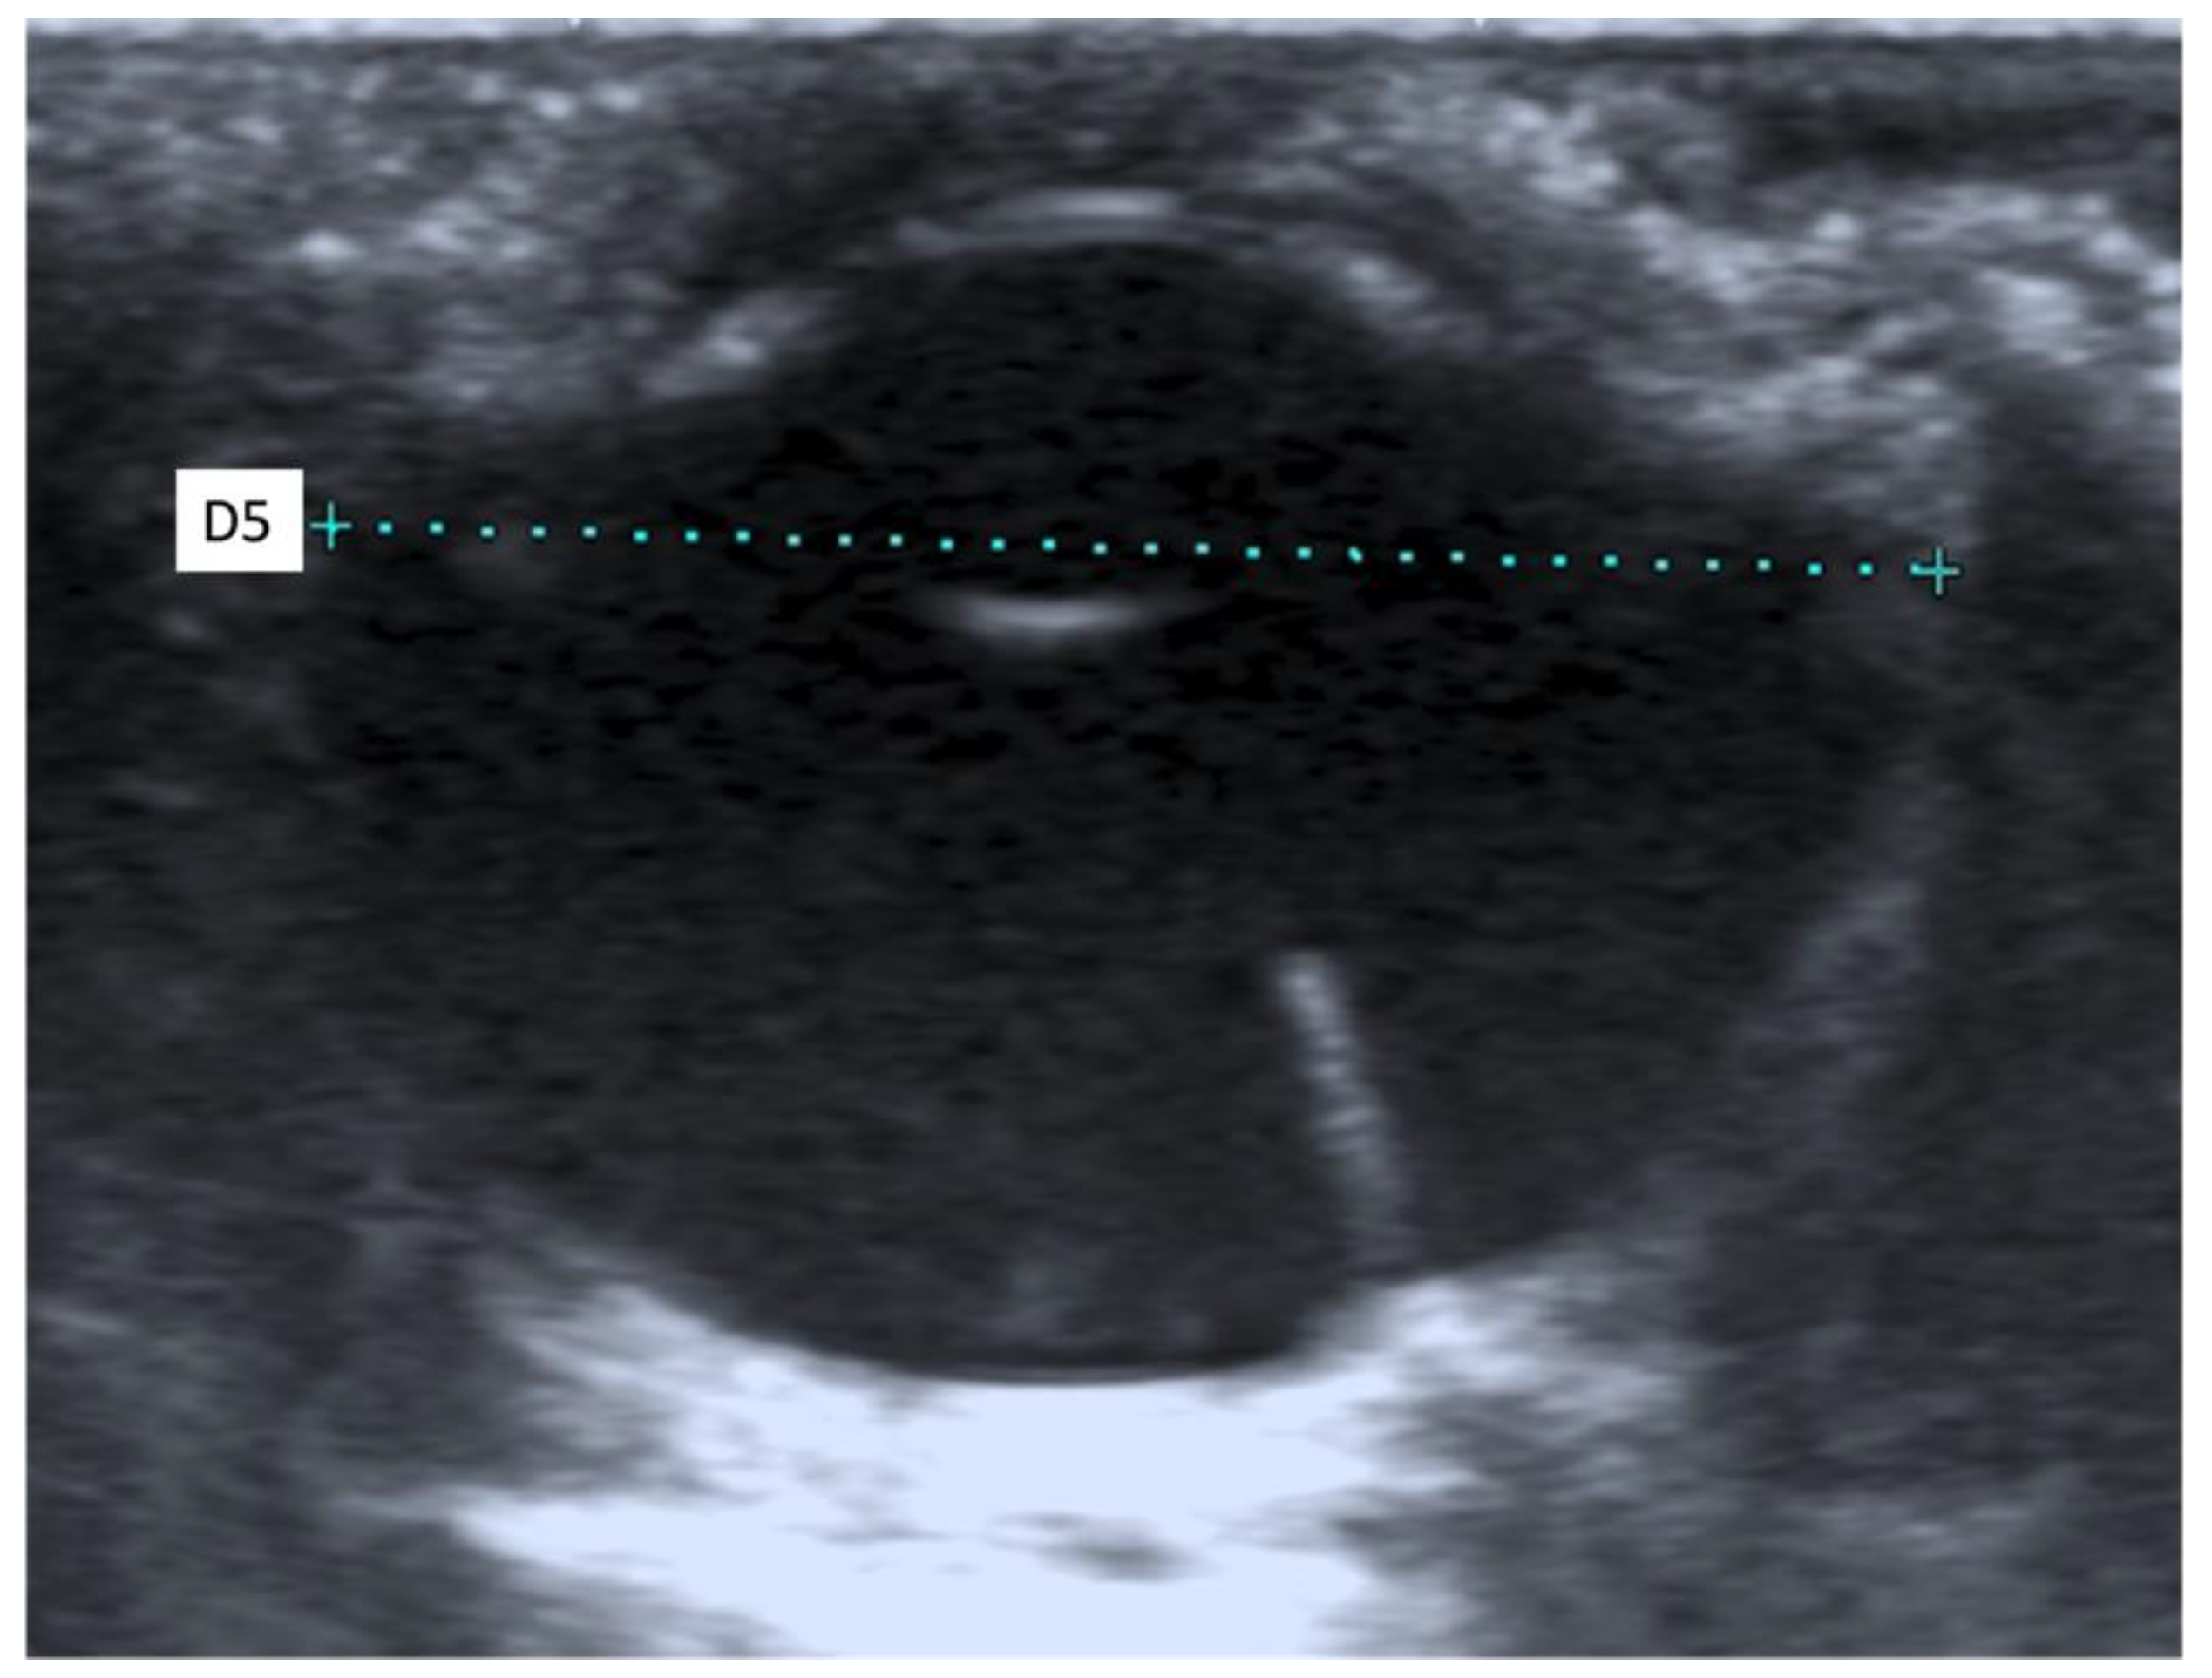

2.4. Ultrasound Biometric Measurements

3.2. Ultrasound Biometric Measurements

| (a) | |||||||||||||||

| Both breeds | OS 1 (n 3 = 27) | OD 2 (n 3 = 27) | Mean OS 1 + Mean OD 2 | ||||||||||||

| D1 5 | D2 6 | D3 7 | D4 8 | D5 9 | D1 5 | D2 6 | D3 7 | D4 8 | D5 9 | D1 5 | D2 6 | D3 7 | D4 8 | D5 9 | |

| Mean (mm) | 1.68 | 7.41 | 4.29 | 15.09 | 18.01 | 1.66 | 7.48 | 4.32 | 15.16 | 18.07 | 1.67 | 7.44 | 4.30 | 15.12 | 18.04 |

| SD 4 (mm) | 0.16 | 0.18 | 0.11 | 0.44 | 0.49 | 0.16 | 0.20 | 0.17 | 0.37 | 0.49 | 0.12 | 0.17 | 0.12 | 0.37 | 0.43 |

| Median (mm) | 1.70 | 7.40 | 4.30 | 15.20 | 18.10 | 1.70 | 7.50 | 4.30 | 15.20 | 18.00 | 1.65 | 7.45 | 4.30 | 15.05 | 18.05 |

| Maximum (mm) | 2.10 | 7.70 | 4.50 | 15.80 | 18.80 | 1.90 | 7.80 | 4.70 | 15.90 | 18.90 | 1.95 | 7.75 | 4.55 | 15.80 | 18.85 |

| Minimum (mm) | 1.40 | 7.00 | 4.10 | 14.30 | 16.80 | 1.30 | 7.10 | 4.10 | 14.60 | 17.30 | 1.45 | 7.05 | 4.10 | 14.50 | 17.25 |